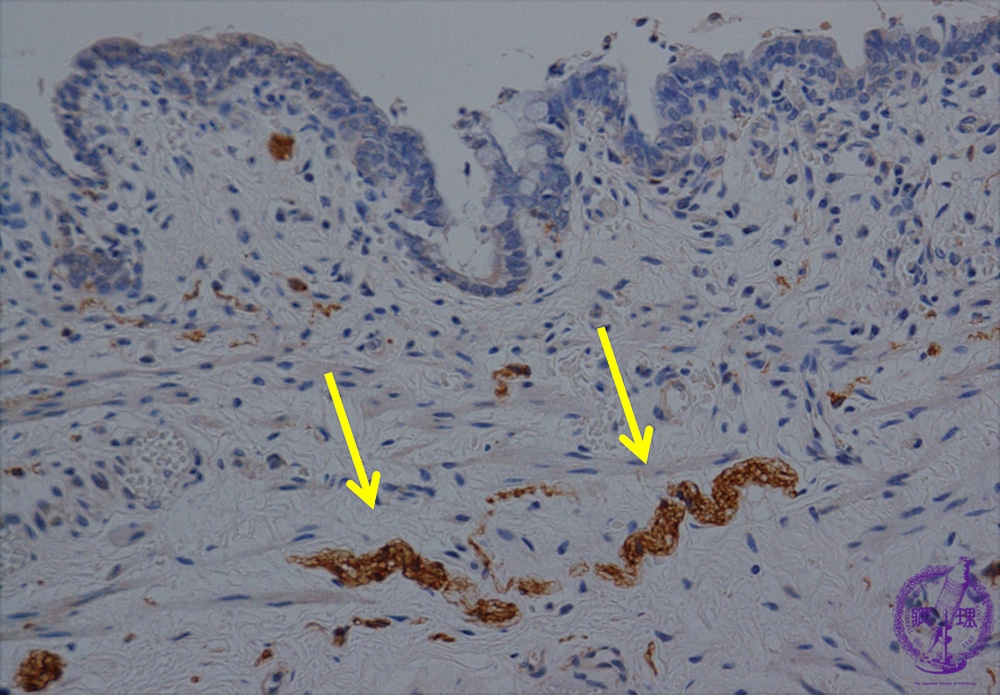

Microscopic view (Acetylcholinesterase stain): Acetylcholinesterase positive nerve fibers are observed in the submucosal layer.

Click the image to see the enlarged image.